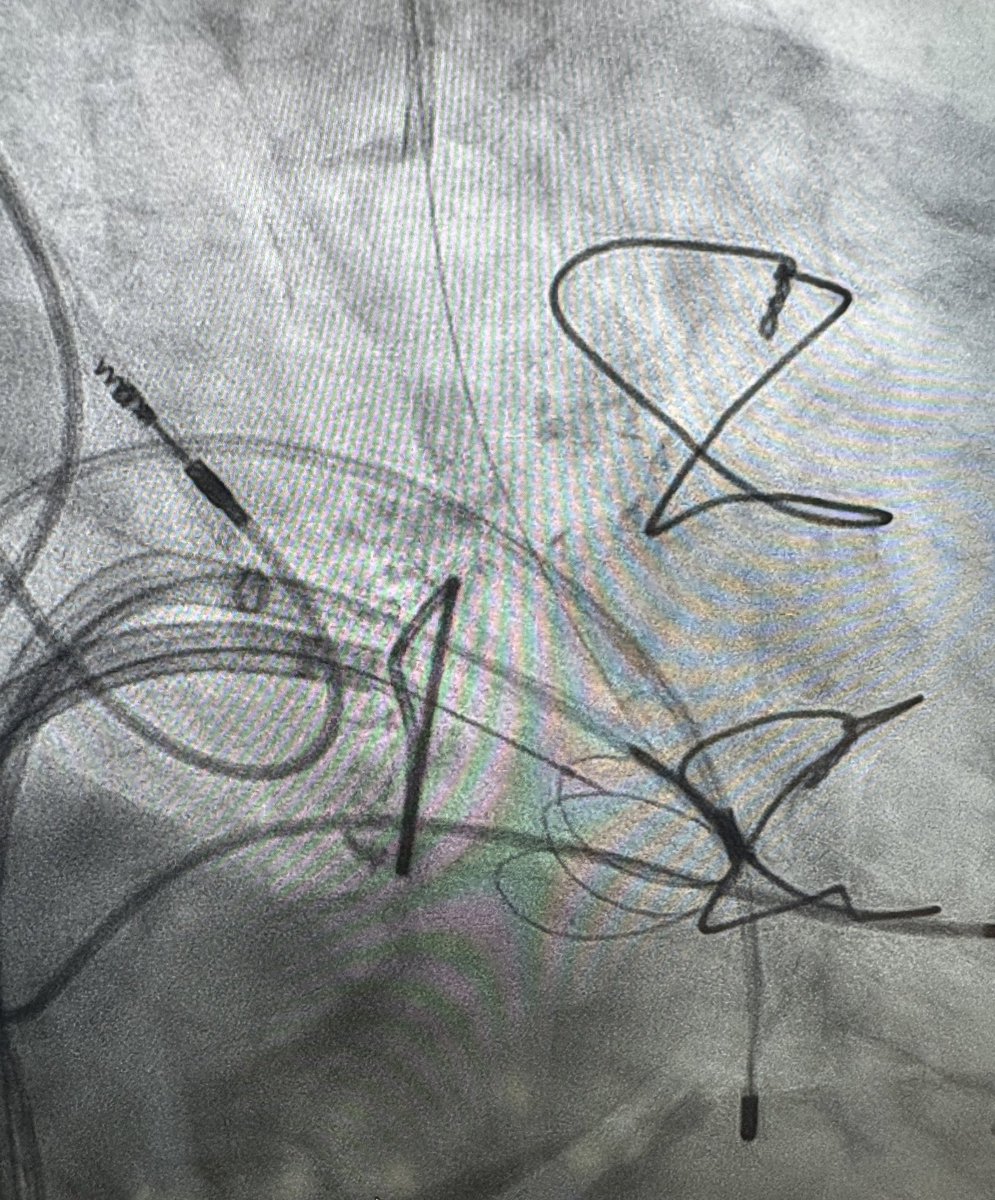

Clip/TEER day with @mhammadah combination of mitral & tricuspid cases, lead free @RAMPARTic happy staff what can go wrong? Ops.. we opened a MitraClip XTW for a TriClip case!! It is ok, put it on the back table use it to take a cool picture! I love the cathlab team @UnivHealthSA

Not the first 2 tricuspid valve clip cases @UTHealthSAValve @UnivHealthSA but the first using the newly approved #Triclip device. Superb outcomes! @mhammadah @drmomani @SouthTexasMed @ladybugs711 #TTEER

Amazing tricuspid clip case by our valve team @mhammadah @drmomani @little_tx using 4D ICE. @UnivHealthSA @UTHealthSAValve @UTHealthcareSA